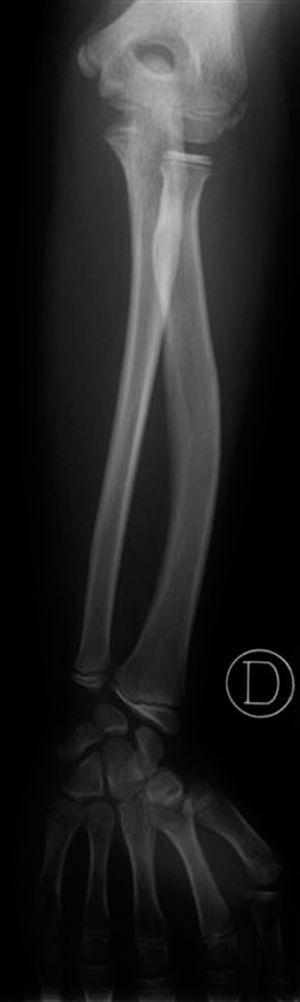

Edad ósea: 6,5 años (Greulich-Pyle). La radiografía practicada con este fin (fig. 2) muestra una imagen de características similares a la de su padre y su hermano (fig. 3).

Figura 3. Radiología de antebrazo y muñeca del hermano, de 13 años.

La figura 3, del antebrazo y muñeca del hermano púber, muestra la semiología displásica completa, sumando los siguientes signos a los ya referidos:

4.Incurvamiento con acortamiento radial.

5.Desviación ulnar de la superficie articular del radio.

6.Deformación triangular de la epífisis radial, cuyo borde externo es llamativamente más grueso que el interno.

A estos signos hay que añadir, en la mitad de los casos, la radiolucencia del borde ulnar distal del radio 1.